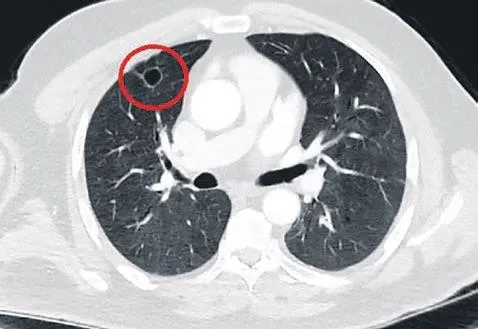

Dr. Fatoş Kozanlı, tedavi sonrası tomografisi çekilen N.T.'nin akciğerindeki tümörün yok olduğunu görünce adeta şok geçirdi. Kozanlı, "Ameliyatı 14 gün erteledik ve hastamıza Coronavirüs tedavisi uygulandı.

Son PCR testi negatif çıktı. Yeni bir tomografi çektik. Tümörün tamamen ortadan kalktığını gördük. Sonuç bilgilerinden başlangıca gittiğimizde, bu bir akciğer kanseri olsaydı, ortadan kalkması mümkün değildi" dedi.